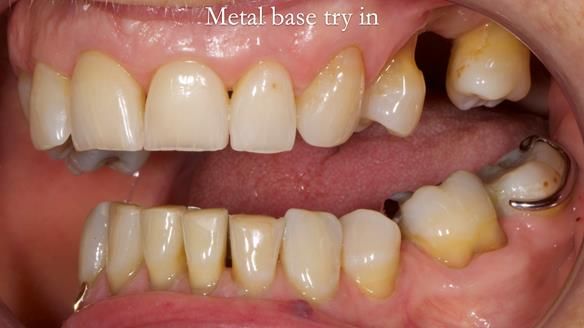

Welcome to Newsletter 61. In this edition, I walk through the process of creating and fitting a metal based lower partial denture for Joyce, a fit and healthy 76 -year-old woman.This issue shows the complete protocol workflow for achieving an exceptionally well-fitted and aesthetically good RPD.

Welcome to Newsletter 61. In this edition, I walk through the process of creating and fitting a metal based lower partial denture for Joyce, a fit and healthy 76 -year-old woman.

The missing lower right teeth to be replaced with a metal based partial denture.

The detailed clinical situation and treatment process are outlined below, with clinical work provided by me and technical work by Rowan Garstang. The treatment spanned six visits for denture fitting and one review.